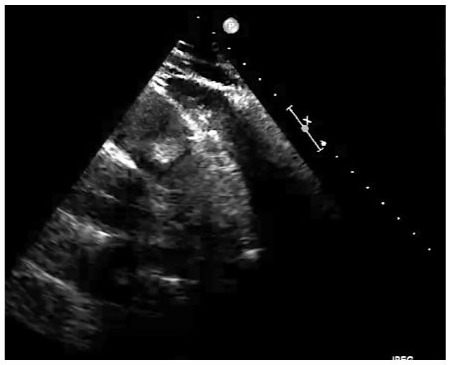

Hemogram, blood chemistry, urine studies, arterial blood gases and coagulation studies were normal. ECG: sinus rhythm, ventricular hypertrophy, incomplete right bundle branch block. RT-PCR for SARS-CoV-2 (COVID-19) negative. Hemocultures (3) of peripheral blood, negative. Echocardiogram: echodense image in the right ventricular outflow tract (RVOT), interpreted as a thrombus; normal ventricular function. Pelvic ultrasound: increased echogenicity in liver due to possible steatosis, simple cystic formations of 5-12 mm in liver and 25 mm in both kidneys. Abdominal-CT, with findings similar to echoes, ruling out abdominal tumours, with evidence of diverticulitis of the left colon (Figure 2).

Figure 2: Transesophageal Echocardiography (TEE) showing the Right Ventricular Outflow Tract (RVOT), the trunk of the pulmonary artery and the pulmonary valve with an obstructive tumour.

With an initial diagnosis of a mass in the right ventricular outflow tract (possible thrombus), the following are performed: Ecotranseophageal, where an echodense mass of 2.5 cm is better appreciated, rounded and with clear limits, with an anchoring in the anterior face of RVOT and that protrudes in each systole to the trunk of the pulmonary artery, regressing in the diastole to the RVOT, with negligible valve regurgitation (possible diagnosis: myxoma in RVOT). CT-angiography shows a hypodense mass in RVOT, adhered to its wall and protruding through the pulmonary valve, with normal trunk, pulmonary arterial branches and parenchyma, and no debris suggesting pulmonary embolisms (a very probable myxoma diagnosis). MRI shows a 20 mm pedunculated mass in RVOT, a slight increase in the signal in T1 and a slight decrease in T2, with moderate prograsive uptake of with gallodinium contrast, for which the radiologist gives us these three diagnoses in decreasing order of suspicion: cardiac papillary fibroelastoma, slow flow hemangioma and myxoma (Figure 3).